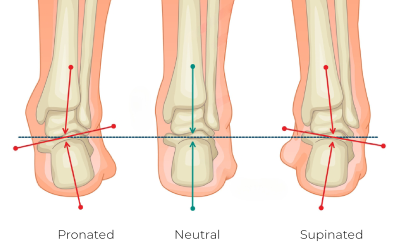

Poor foot mechanics can have a substantial impact on the entire body (Image 2). The feet are the foundation of the body, and a problem at the base can lead to a cascade of compensatory changes up the kinetic chain. For example, pes planus (flat feet) causes overpronation and leads to internal rotation of structures of the lower extremities, affecting the knees, hips, and back. Pes cavus (high arches) can lead to oversupination, contributing to issues like plantar fasciitis and shin splints.